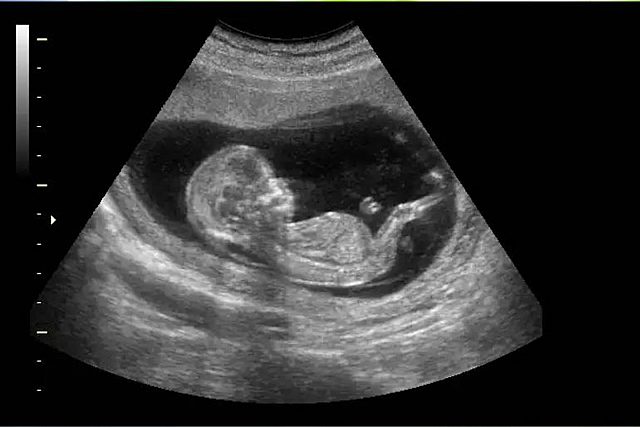

• Ultrasounds

Ultrasounds

It was invented in the XX century by physic P. Langevin and the doctor C.Chilowsky.

This was invented to detect problems that wasn´t able to watch outside s this makes an ultrsound of the inside of the body.